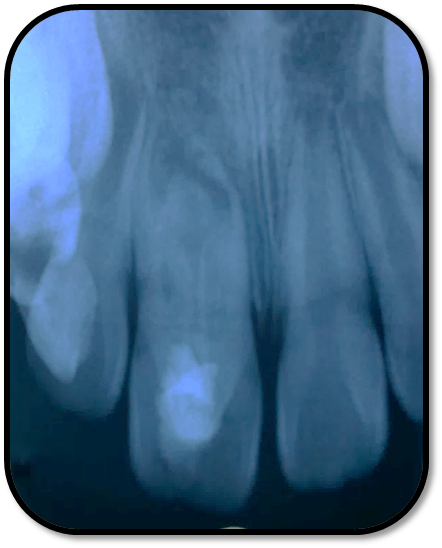

随访复查: 治疗完成后1个月复查:右上1临床检查无阳性体征,叩痛(—),冷测无反应,无松动,牙龈无红肿,充填物完好,牙冠略有变色, X线检查:牙根根继续发育,可见钙化影像形成,如图示 治疗完成后7个月复查:临床检查无阳性体征,充填物完好,牙冠变色局部发黑,叩痛(—),冷测无反应,无松动,牙龈无红肿,临床及 X线检查:牙根继续发育,如图示 治疗完成后17个月复查:临床检查无阳性体征,充填物完好,牙冠变色局部发黑,叩痛(—),冷测无反应,无松动,牙龈无红肿。X线:牙根继续发育,根尖孔已近闭合。如图。 讨论: